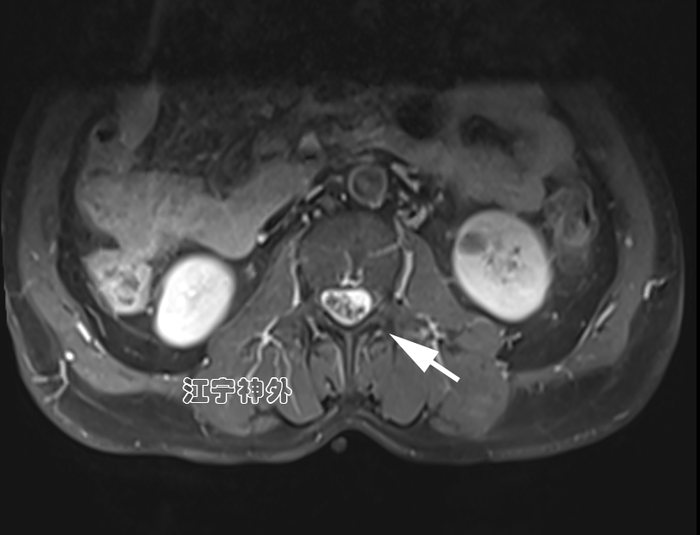

郑主任阅片发现,从横断面来看,肿瘤几乎占据了椎管全径,正常的脊髓圆锥和神经根已不可辨认,很难说是髓外硬膜下病变还是髓内病变。结合病程很长,脑脊液循环已完全阻断,推测肿瘤与脊髓圆锥、马尾神经根之间,以及肿瘤与硬脊膜之间很可能有明显粘连,所以手术难度较大,手术风险高。

经过充分的术前准备,郑学胜团队于2月16日在术中电生理监测下实施椎管肿瘤切除术;结果手术难度比预估的还要更大,因为不仅肿瘤质地很硬、血供丰富,而且肿瘤位于脊髓圆锥和神经根的腹侧,手术只能在圆锥和神经根的间隙里操作,肿瘤的腹侧又与硬脊膜严重粘连;郑学胜团队经过近6小时的手术,终于将肿瘤完整全切,并且脊髓圆锥和神经根保护良好。